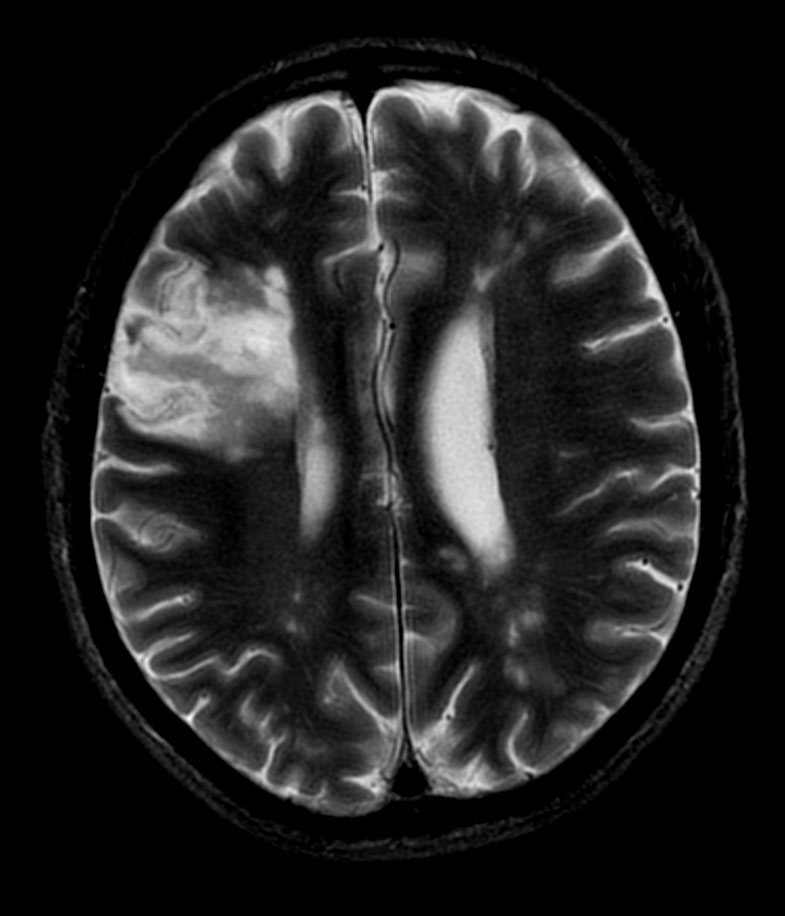

Patient with multiple brain lesions. The ExamCard includes Compressed SENSE to accelerate the entire exam and techniques for motion reduced imaging (MultiVane XD), 3D imaging to acquire high resolution data in multiple directions, 3D susceptibility weighted imaging (SWIp), DWI with EPIC Brain to bring down any residual distortion and Computed DWI to generate synthetic high b-value images.

T2w TSE MultiVane XD